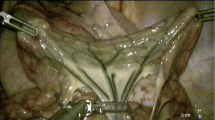

Thirty-seven parathyroid glands from 21 different patients were included in this study. Label-free imaging (LSCI & NIRAF) and ICG imaging were performed using a previously developed parathyroid speckle and autofluorescence imager (ParaSPAI)40, shown in Fig. 1. Representative images of a well-perfused and a devascularized parathyroid gland are displayed in Fig. 2. Both sets of images were acquired in a thyroid lobectomy case.

Representative white light, near-infrared autofluorescence (NIRAF), indocyanine green (ICG) fluorescence, and speckle contrast images of a devascularized (A–D) and a well-perfused (E–H) parathyroid gland, acquired with the imaging device. The parathyroid glands are indicated with white ellipses in white light and ICG fluorescence images, and with dotted contours generated by automated segmentation in NIRAF and speckle contrast images.